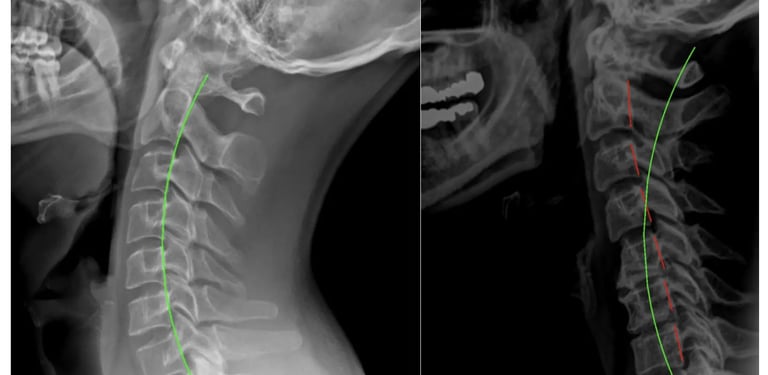

Precise X-Ray Reports

We use state-of-the-art technology from PostureRay to visualize your digital x-rays to measure spinal alignment and determine exactly what type of care is right for you.